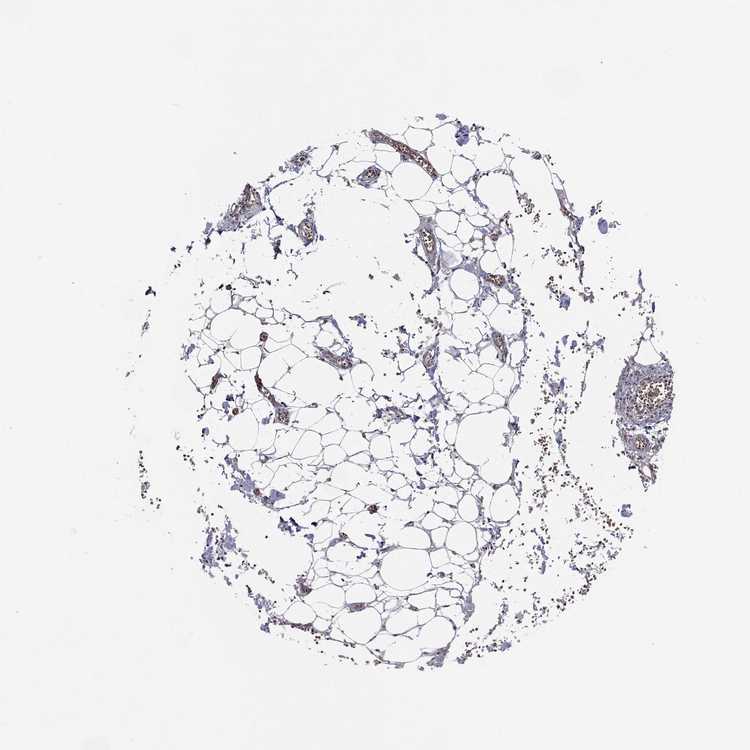

SOFT TISSUE 2 - Antibody stainingi

Antibody staining in the annotated cell types in the current human tissue is reported as not detected, low, medium, or high, based on conventional immunohistochemistry profiling in selected tissues. This score is based on the combination of the staining intensity and fraction of stained cells.

Each image is clickable and will lead to virtual microscopy that enables deeper exploration of all samples and also displays staining intensity scores, fraction scores and subcellular localization as well as patient and tissue information for each sample.

Antibody HPA050166Antibody HPA076046

Chondrocytes Low-

Fibroblasts MediumLow

Peripheral nerve -Not detected